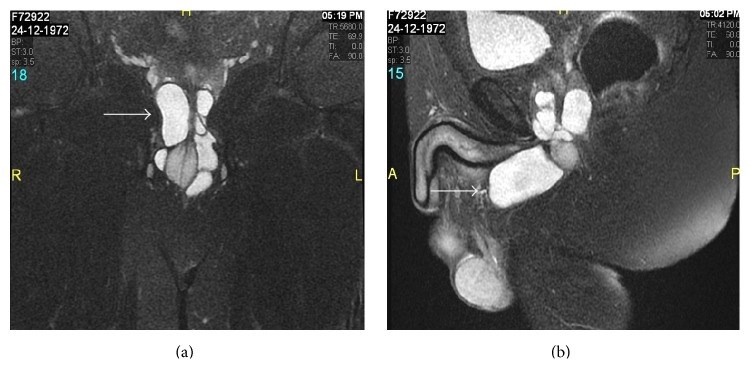

Cowper's gland syringocele is an uncommon, underdiagnosed cystic dilatation of Cowper's gland ducts showing various radiological patterns. Herein we report a rare case of giant Cowper's gland syringocele in an adult male patient, with description of MRI findings and management outcome.